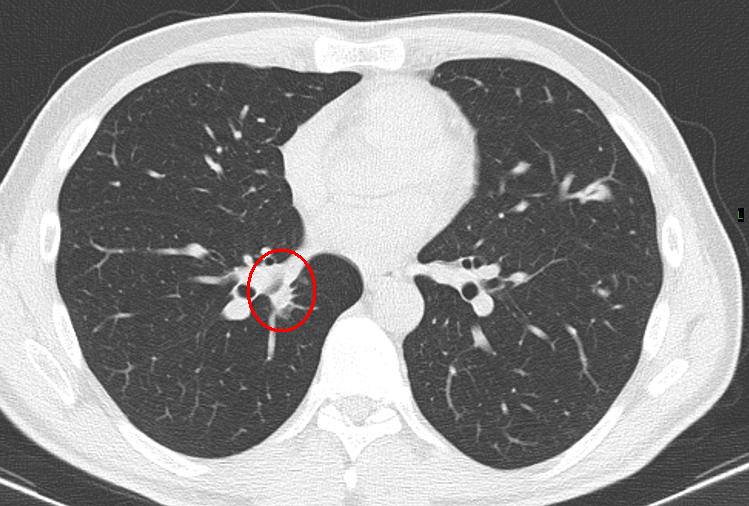

Figure 1 from CT features of lung scar cancer. Semantic Scholar Scar Tissue Lung After Pneumonia These changes make it harder for oxygen to pass into the bloodstream. Images of the chest may show the scar tissue that is usually part of pulmonary fibrosis. Pulmonary fibrosis (pf) is a process that causes lung scarring, in which fibrotic tissue blocks the movement of oxygen from inside the tiny air sacs in the lungs into the bloodstream. Over. Scar Tissue Lung After Pneumonia.

Incidental Scar Carcinoma Right Lung Chest Case Studies CTisus CT Scanning Scar Tissue Lung After Pneumonia Pulmonary fibrosis (pf) is a process that causes lung scarring, in which fibrotic tissue blocks the movement of oxygen from inside the tiny air sacs in the lungs into the bloodstream. Pulmonary fibrosis is a serious, lifelong lung disease. Over time, due to combination of genetic and environmental factors like pollution or cigarette smoke. Lung scarring changes the normally thin. Scar Tissue Lung After Pneumonia.

Scar Carcinoma in Right Lower Lung Chest Case Studies CTisus CT Scanning Scar Tissue Lung After Pneumonia Images of the chest may show the scar tissue that is usually part of pulmonary fibrosis. Lung scarring changes the normally thin tissue in the lungs into thick, scarred tissue. It causes lung scarring (tissues scar and thicken over time), making it harder to. These changes make it harder for oxygen to pass into the bloodstream. Pulmonary fibrosis (pf) is. Scar Tissue Lung After Pneumonia.